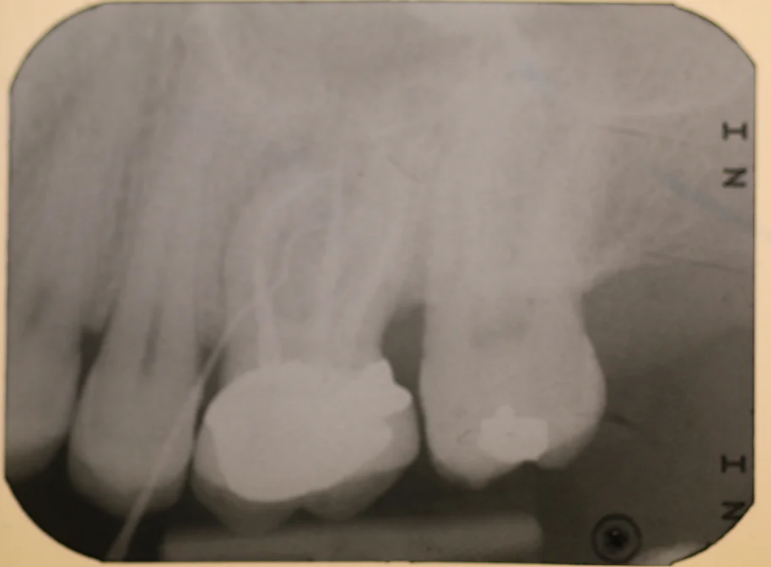

Case 12 – Implants

Molar with failed root filling replaced with an implant.